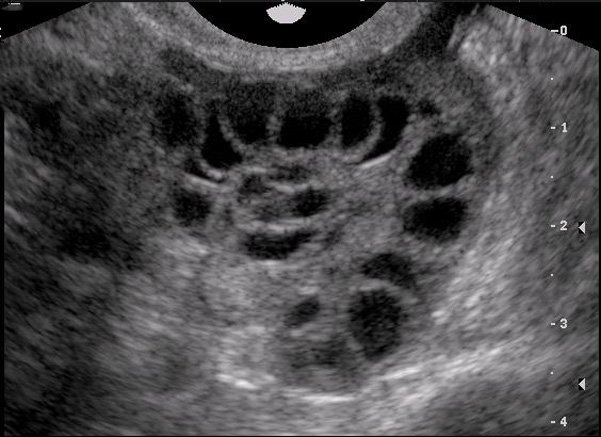

- Tăng kích thước của buồng trứng

- Phụ nữ có các bệnh lý liên quan đến buồng trứng, như u buồng trứng hoặc polycystic ovary syndrome (PCOS).